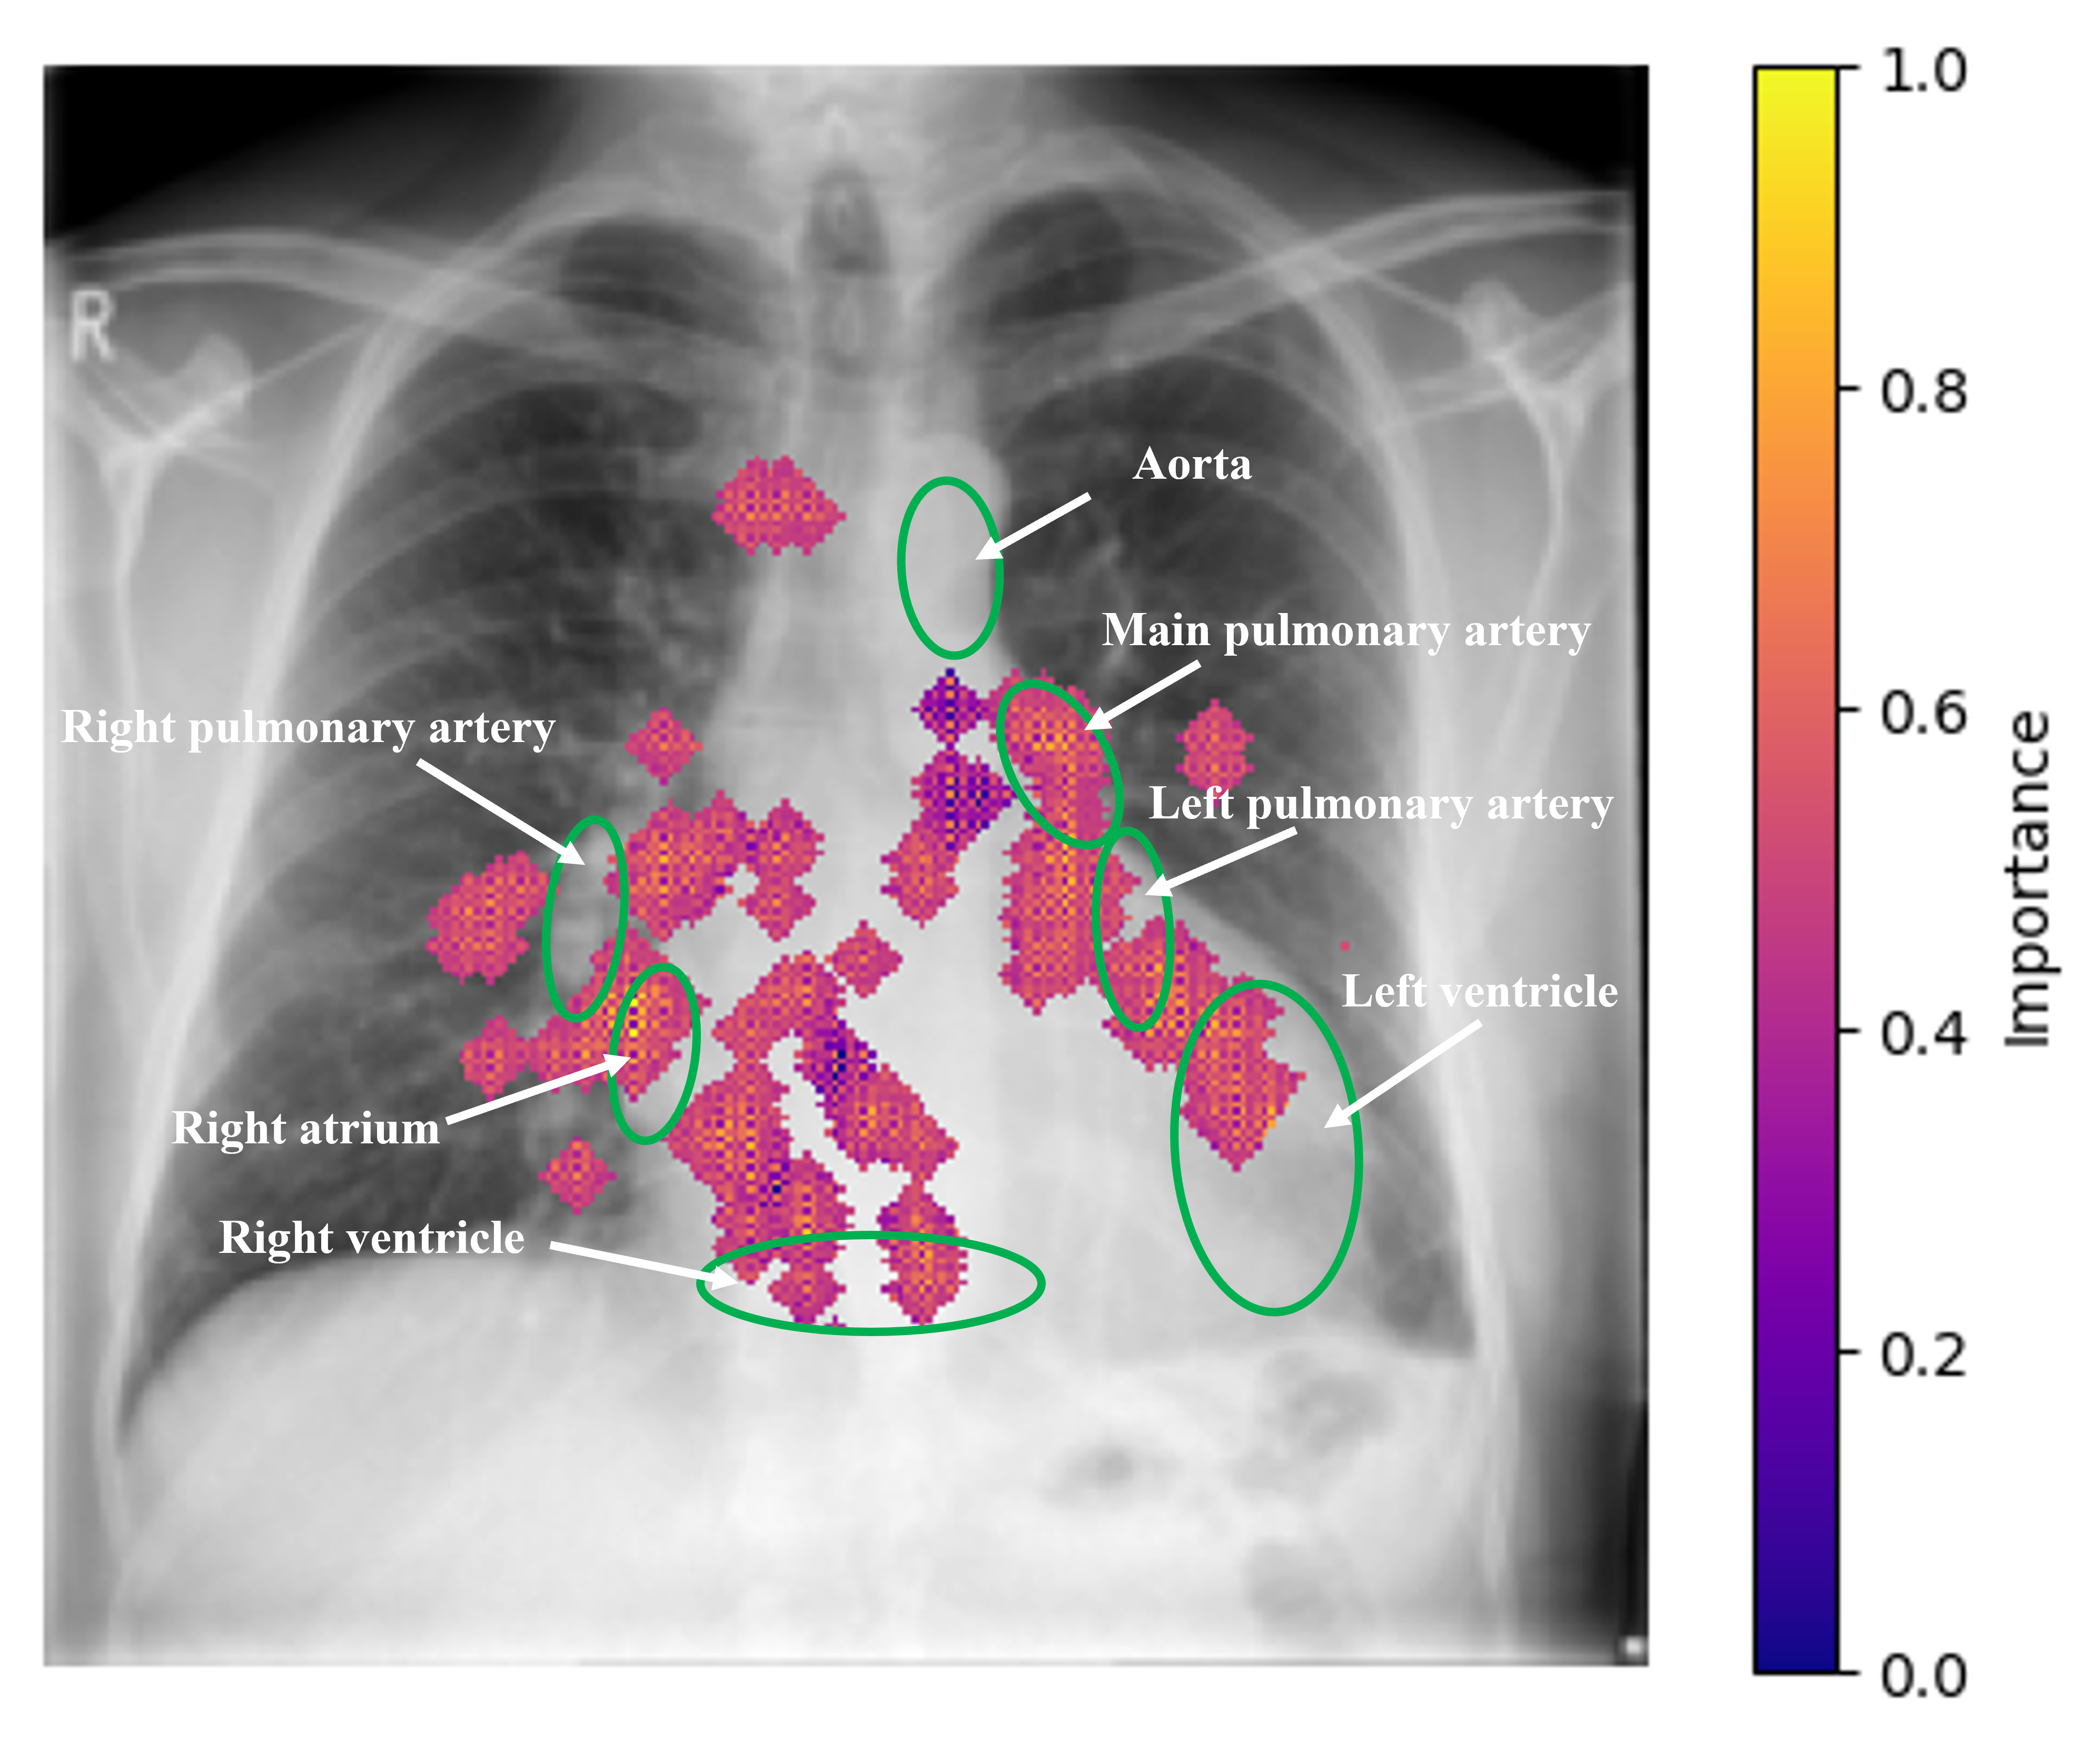

Figure 2: Interpretability of CardioVAEX,GsubscriptCardioVAEX,G\text{CardioVAE}_{\text{X,G}} for two subjects using integrated gradients method [24]. (a) 1D ECG (top left) and CXR (bottom left) for normal PAWP, (b) 1D ECG (top right) and CXR (bottom right) for elevated PAWP. Green annotations on CXRs highlight seven regions of the heart and lungs, marked by an expert clinician for enhanced visualization of key areas. The 1D ECG signal was smoothed with NeuroKit2 [19] library for better visualization.

Model Interpretation: We used the integrated gradients method [24] to demonstrate the interpretability of our best performing CardioVAEX,GsubscriptCardioVAEX,G\text{CardioVAE}_{\text{X,G}} model with both CXR and ECG modalities. Fig. 2 depicts important regions for a normal subject and an abnormal subject, as identified by our model’s decisions. For ECG, the model focuses on R𝑅R peak (for normal PAWP) as shown in zoomed-in segments, whereas the model relies on R𝑅R and S𝑆S peaks for abnormal PAWP. This indicates that our model performs the prediction based on QRS complex region [13]. The distinct alterations in the QRS complex enable the identification of left ventricular structural changes and conduction abnormalities, which are closely linked to variations in PAWP, reflecting the heart’s response to altered cardiac hemodynamic states. In CXR images, the model focuses on cardiac regions, i.e. the left and right ventricles and arteries. By examining these regions in CXR, the model identifies their enlargement or structural changes, important indicators of cardiac function and fluid status. This offers important insights into PAWP levels by detecting subtle radiographic features of cardiac hemodynamic shifts and ventricular pressure alterations.